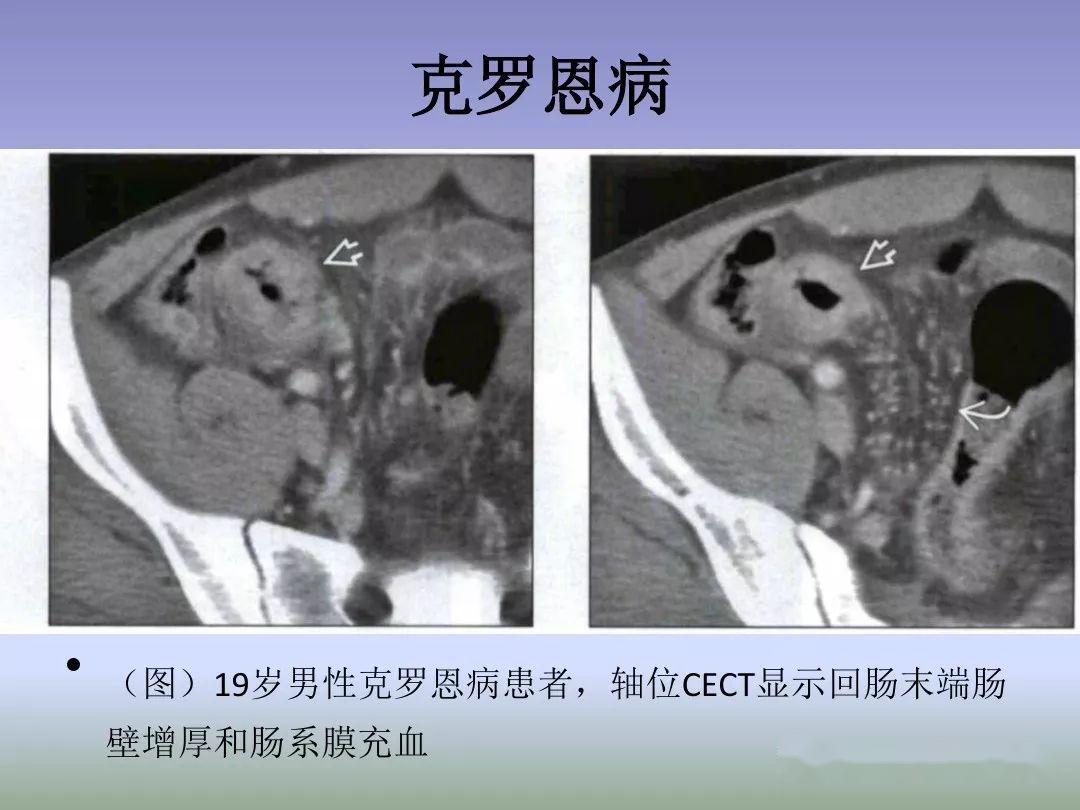

回盲部解剖特点及其病变的影像诊断